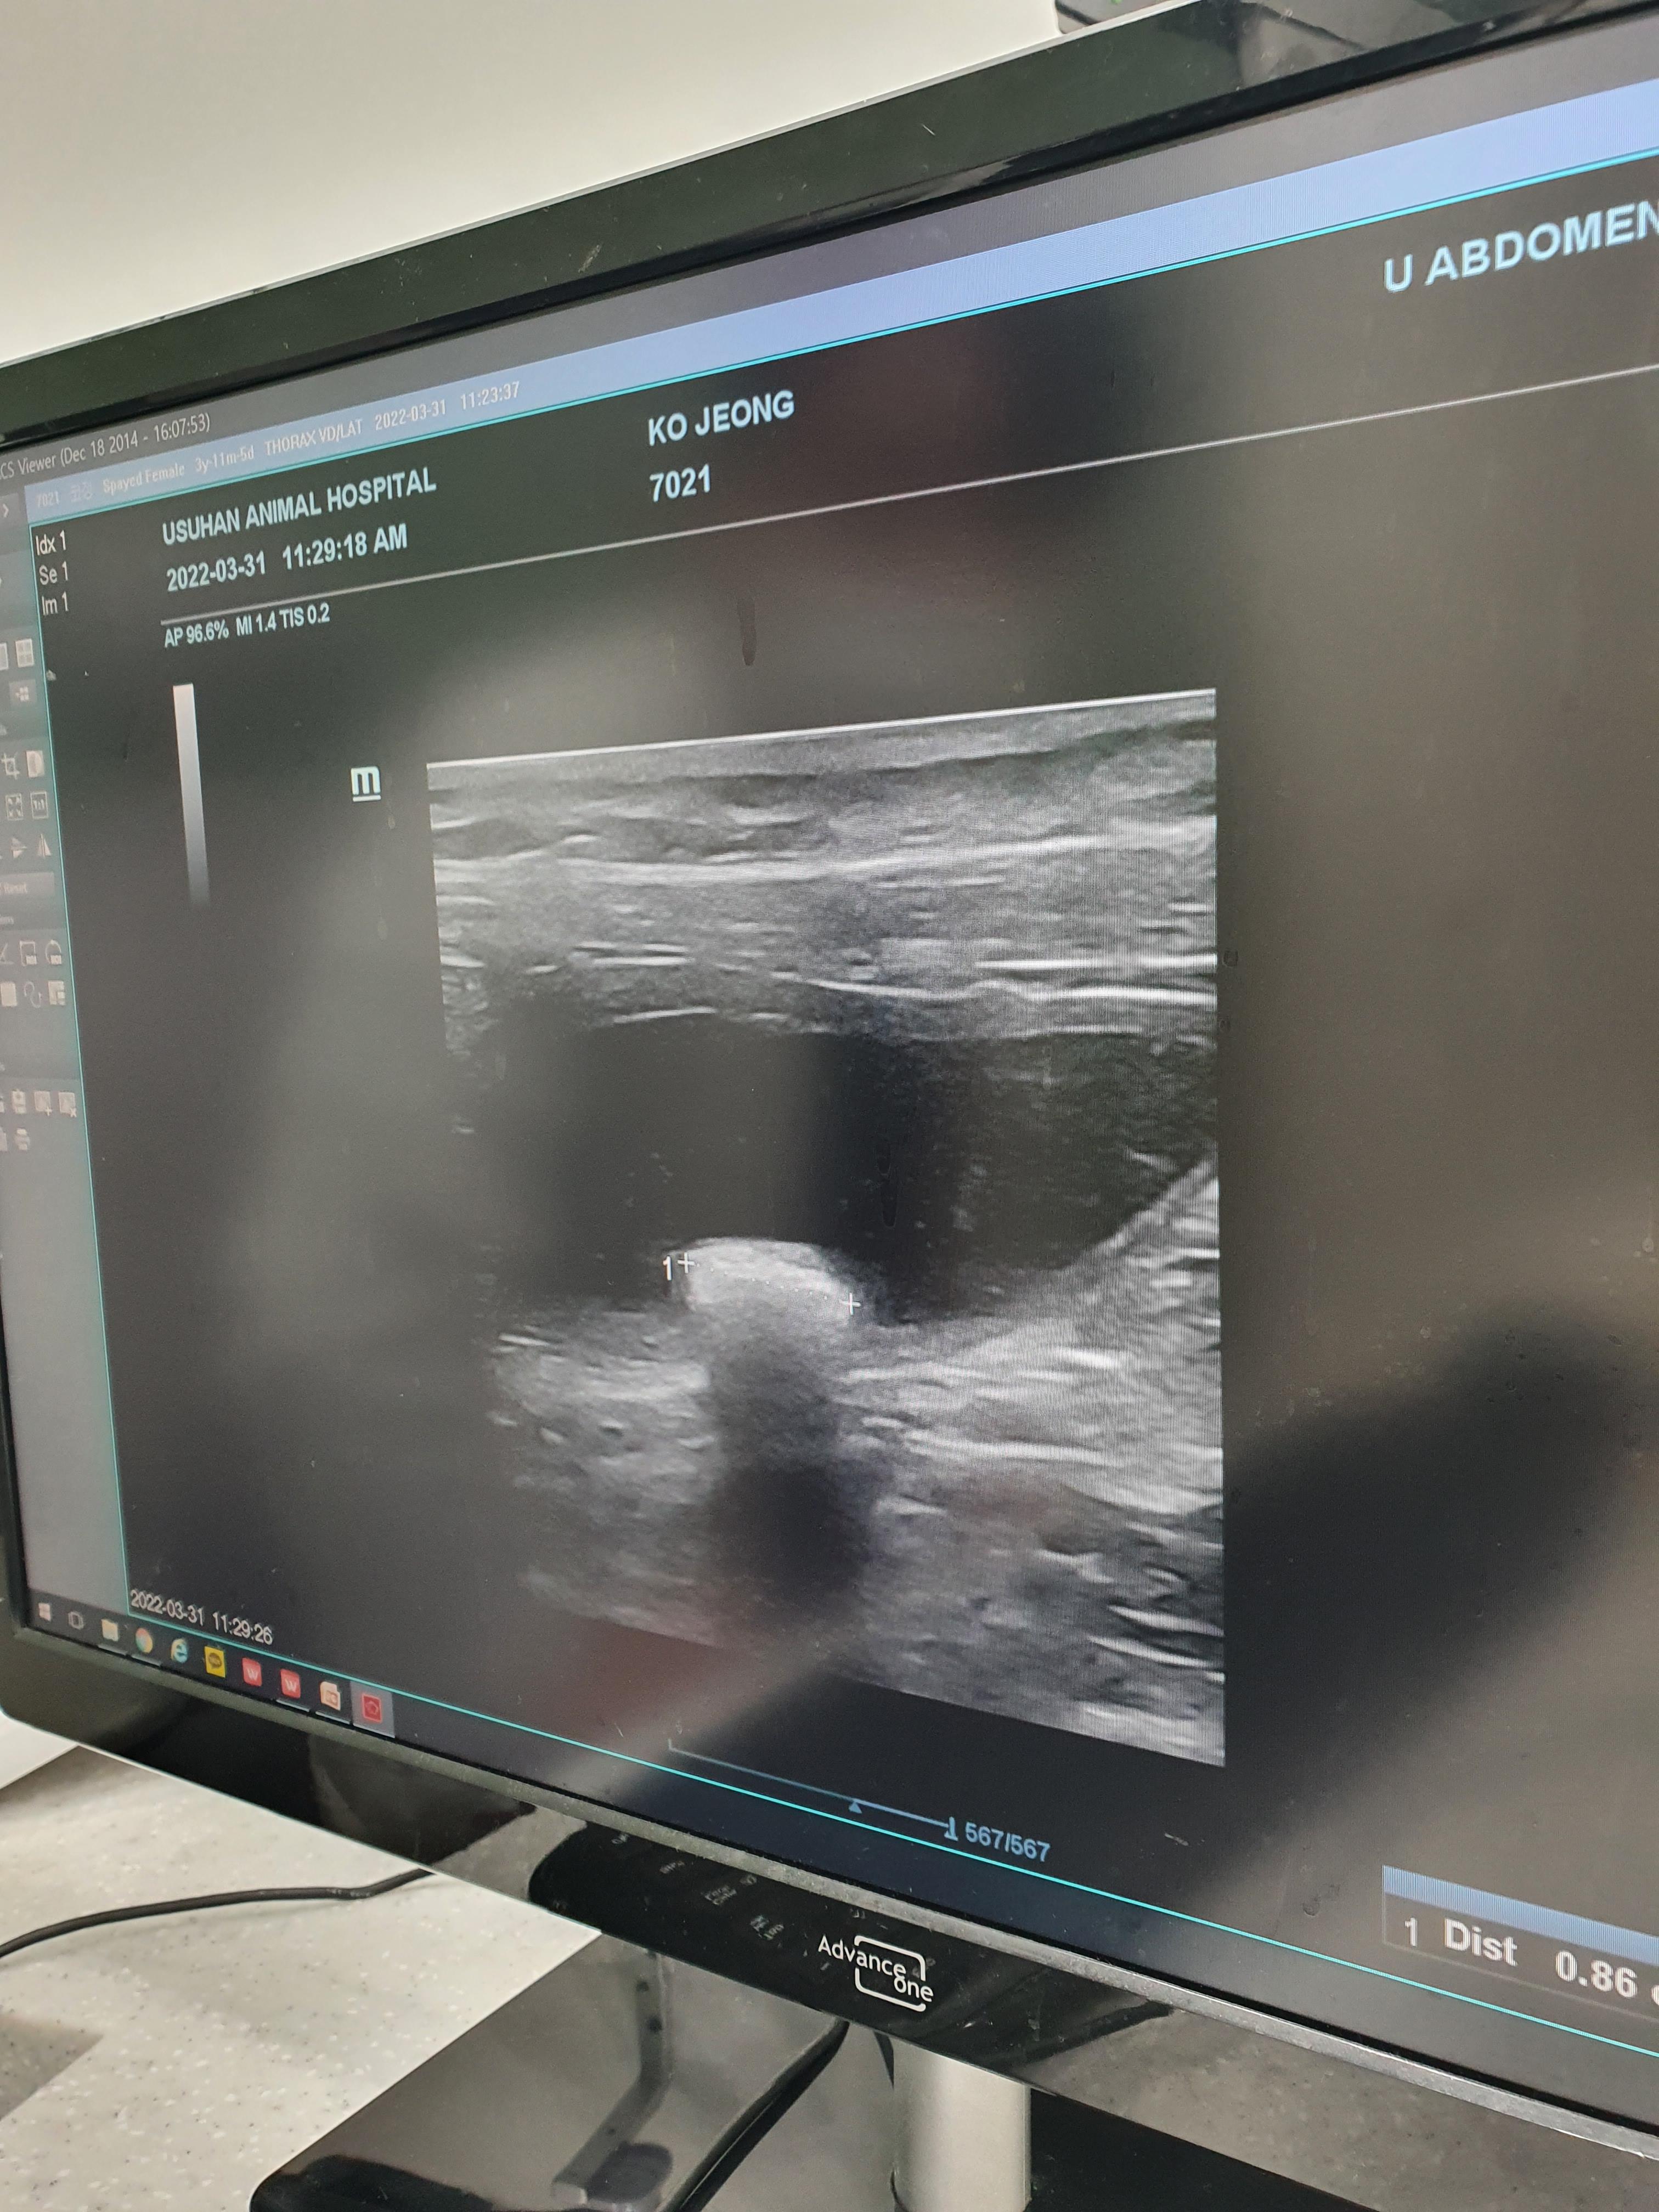

안고 들어가서 방광초음파와 엑스레이를 찍고 나왔다.

초음파에 약 0.9mm 사이즈의

결석이 발견됐다고 하셨다.

엑스레이상으로도 너무 또렷이 보였다.